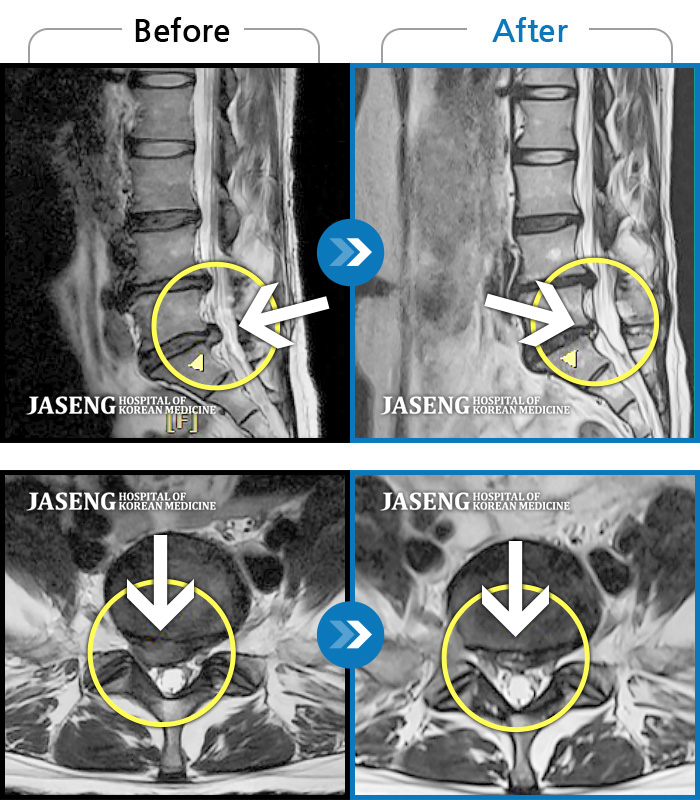

허리디스크

도움받은 사례

광주 · 장영우 원장

양측 허리의 묵직한 통증 및 기침 시 증상이 심화되어 내원하셨습니다.

촬영시기

2024.12.09 ~ 2025.05.24

2025.06.05

조회수 237